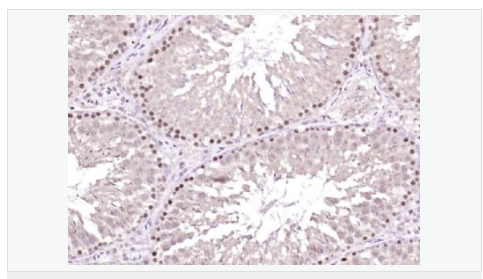

| 產品應用 | ELISA=1:5000-10000 IHC-P=1:100-500 IHC-F=1:100-500 IF=1:100-500 (石蠟切片需做抗原修復) not yet tested in other applications. optimal dilutions/concentrations should be determined by the end user. |

| 產品介紹 | The protein encoded by this gene is a member of the BTG/Tob family. This family has structurally related proteins that appear to have antiproliferative properties. This encoded protein might play a role in neurogenesis in the central nervous system. Two transcript variants encoding different isoforms have been found for this gene. [provided by RefSeq, Aug 2008]. Function: Overexpression impairs serum-induced cell cycle progression from the G0/G1 to S phase. Subunit: Interacts with KCNMA1 tetramer. There are probably 4 molecules of KCMNB1 per KCNMA1 tetramer. Subcellular Location: Membrane; Multi-pass membrane protein. Tissue Specificity: Abundantly expressed in smooth muscle. Low levels of expression in most other tissues. Within the brain, relatively high levels found in hippocampus and corpus callosum. Similarity: Belongs to the KCNMB (TC 8.A.14.1) family. KCNMB1 subfamily. SWISS: Q14201 Gene ID: 10950 Database links: Important Note: This product as supplied is intended for research use only, not for use in human, therapeutic or diagnostic applications |